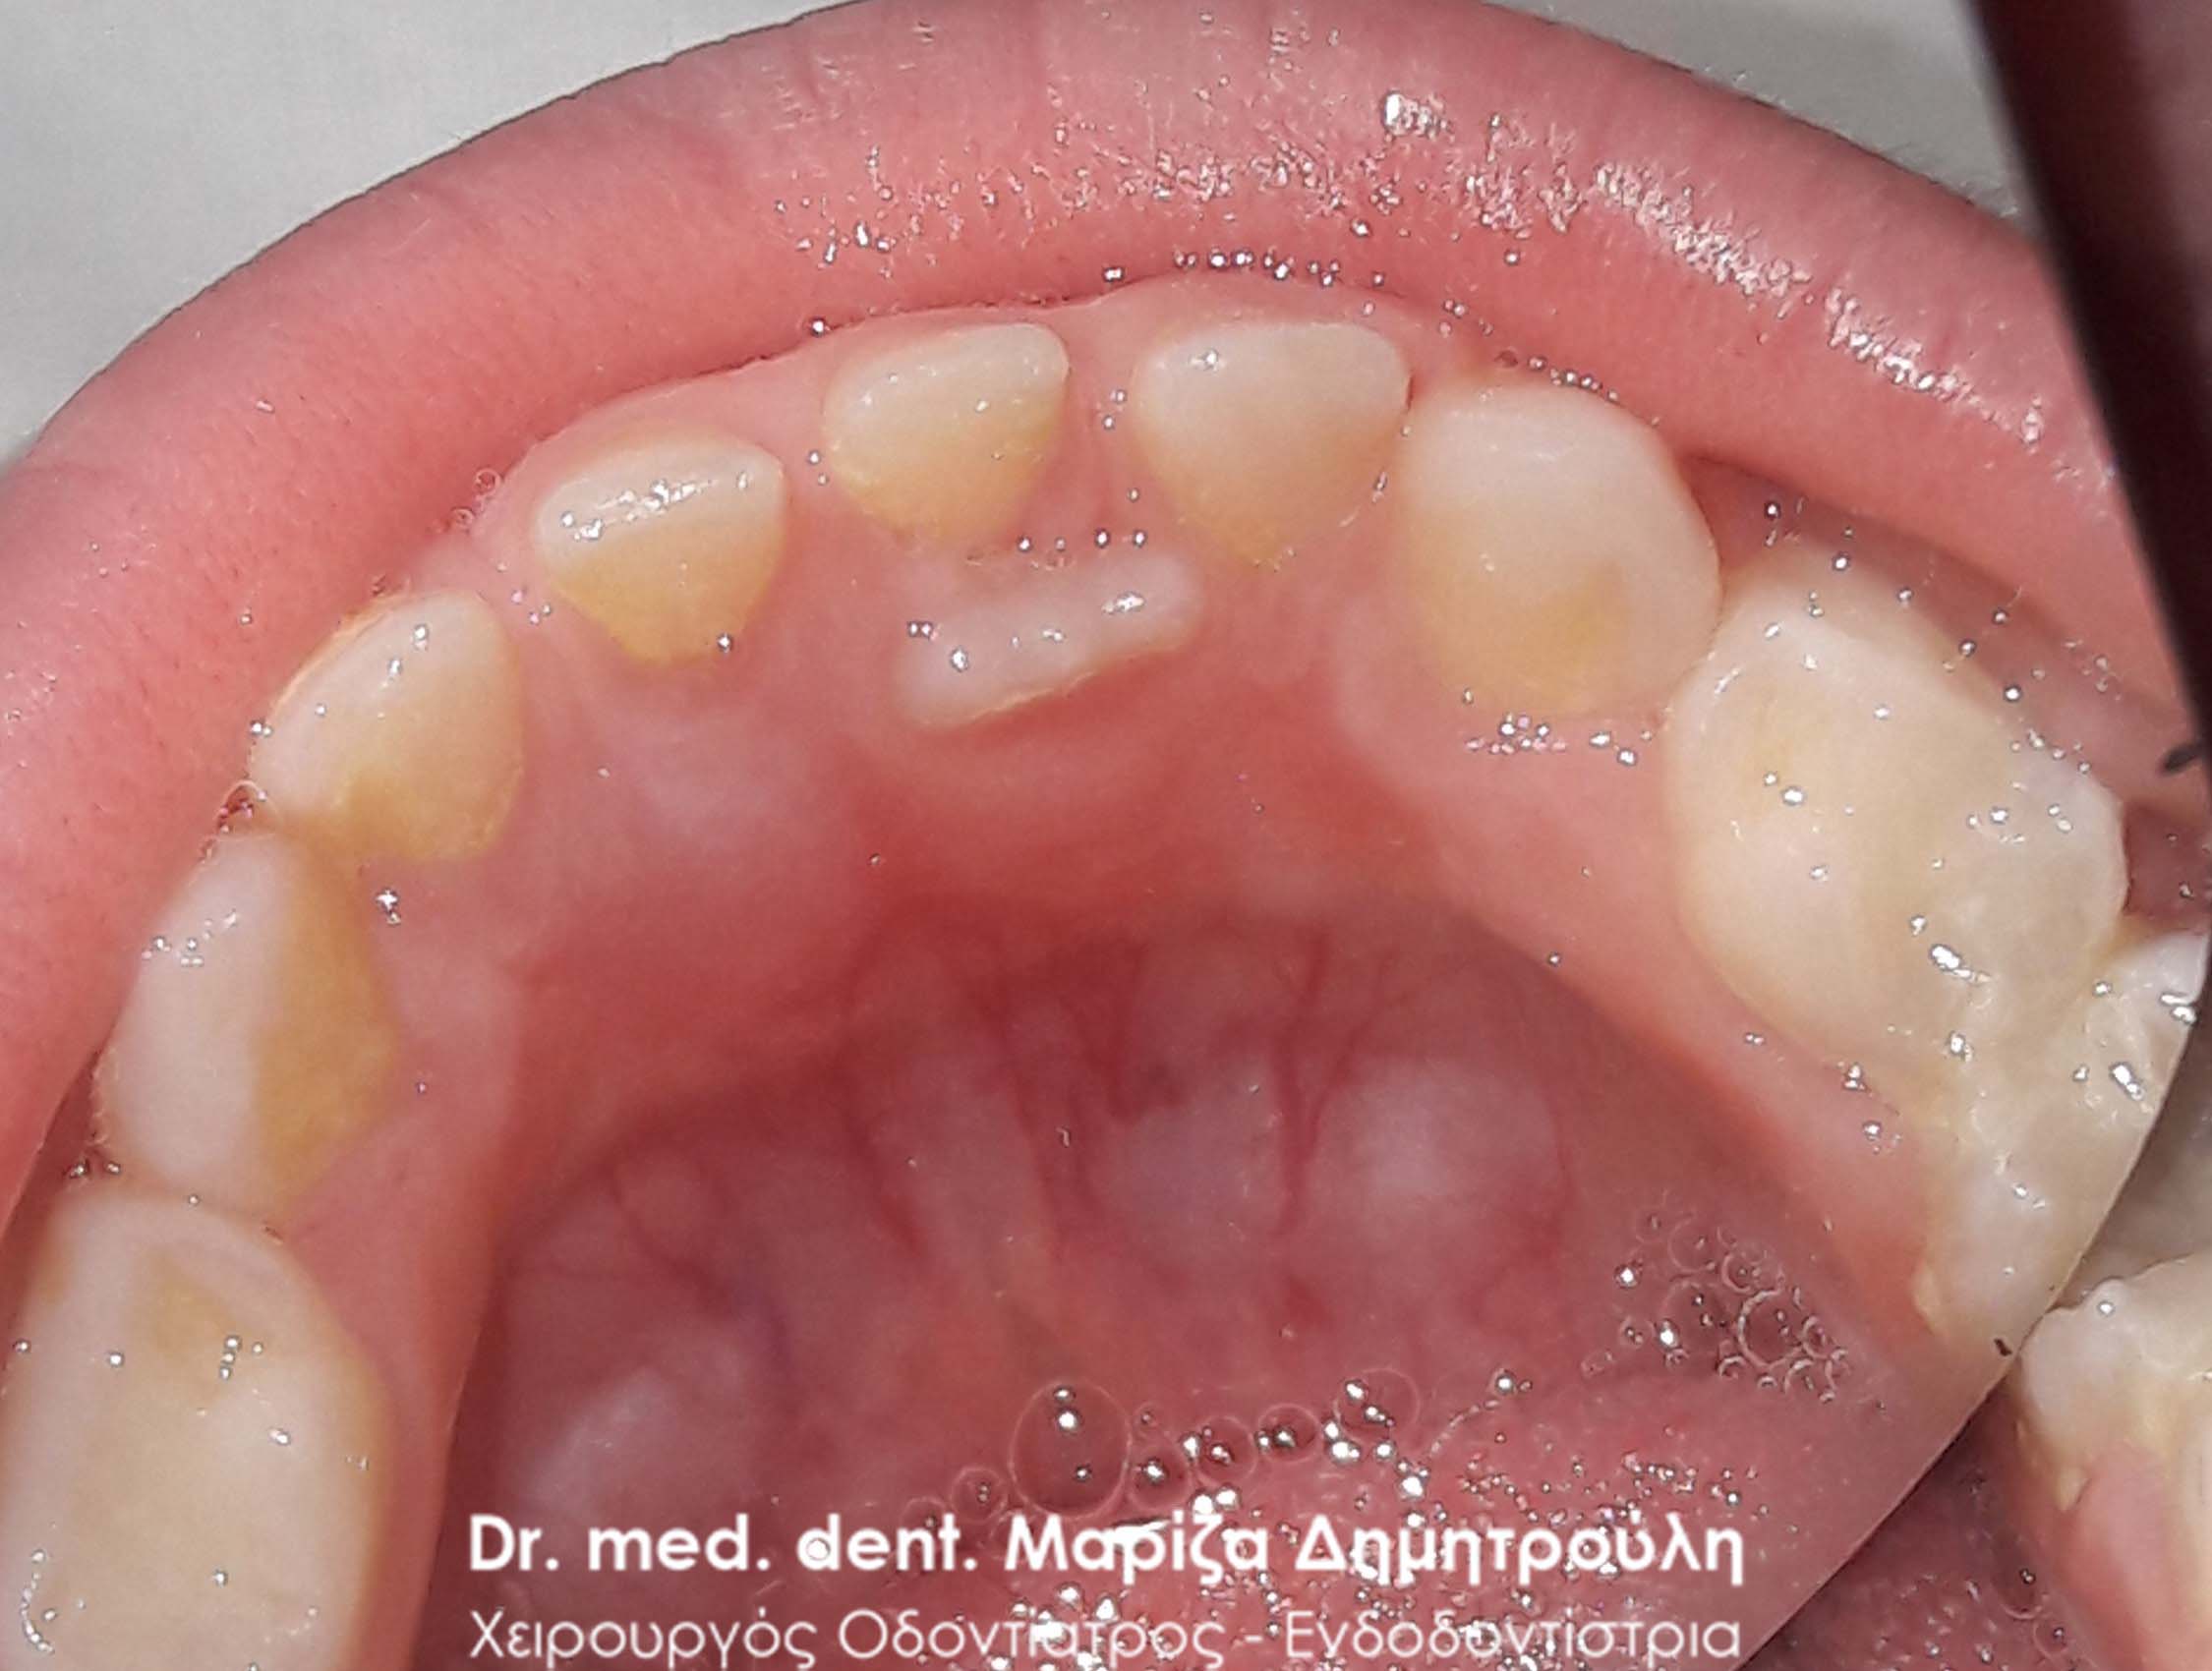

Περιστατικό – Εξαγωγή νεογιλού δοντιού με ολόκληρη ρίζα

Τα νεογιλά δόντια με το πέρασμα των χρόνων αρχίζουν να κουνιούνται, πέφτουν και αντικαθίστανται από τα αντίστοιχα μόνιμα δόντια. Απαραίτητη προϋπόθεση για όλη αυτή τη διαδικασία είναι η απορρόφηση της ρίζας του εκάστοτε νεογιλού δοντιού. Υπάρχουν όμως περιπτώσεις στις οποίες η ρίζα των νεογιλών δοντιών δεν απορροφάται με αποτέλεσμα τα νεογιλά δόντια να παραμένουν στη θέση τους ενώ συγχρόνως τα μόνιμα δόντια κάνουν την εμφάνιση τους στο στόμα του μικρού παιδιού. Σε τέτοιου είδους περιστατικά είναι απαραίτητη η εξαγωγή του νεογιλού δοντιού, ώστε το μόνιμο δόντι να πάρει την τελική του θέση στο παιδικό στόμα.

Στο συγκεκριμένο περιστατικό που παρουσιάζεται ο νεογιλός κυνόδοντας παρέμενε στη θέση του, ενώ ταυτόχρονα είχε ανατείλει ο μόνιμος κυνόδοντας. Μετά την αναγκαία εξαγωγή του νεογιλού δοντιού διαπιστώθηκε οτι δεν υπήρξε καμία φυσιολογική απορρόφηση της ρίζας του δοντιού με αποτέλεσμα το δόντι να παραμένει παραπάνω από το φυσιολογικό στο στόμα. Μετά την αφαίρεση του δοντιού ο μόνιμος κυνόδοντας πήρε την τελική φυσιολογική θέση σε διάρκεια ενός μηνός.